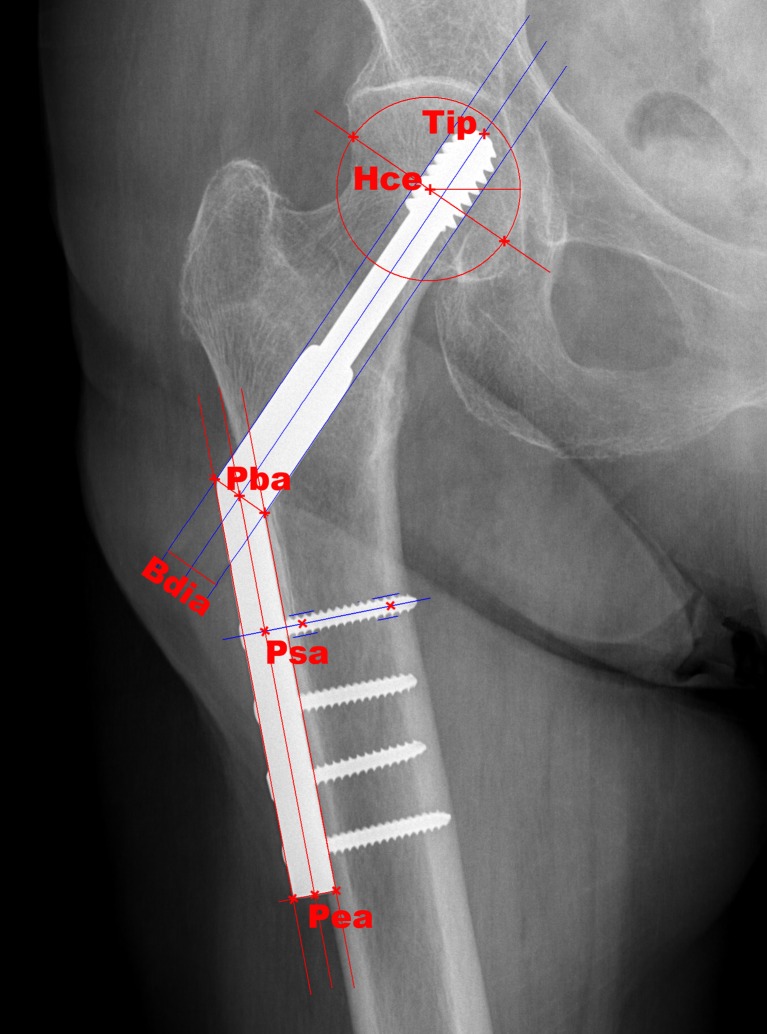

In order to align radiographic measurements according to the plate length axis, a coordinate system centred at the “plate barrel axis” (Pba point), i.e., the intersection between the mid-axes of the plate and barrel was applied (Fig. 1). All point coordinates were transformed using trigonometric formulae so the plate middle axis and thus all Y coordinates are presented in a vertical manner, while X coordinates are presented horizontally.

Radiographic landmark points on anteroposterior (AP) view. Tip DHS® tip, Hce head centre, Pba plate barrel axis, Bdia barrel diameter, Psa plate screw axis, Pea plate end axis